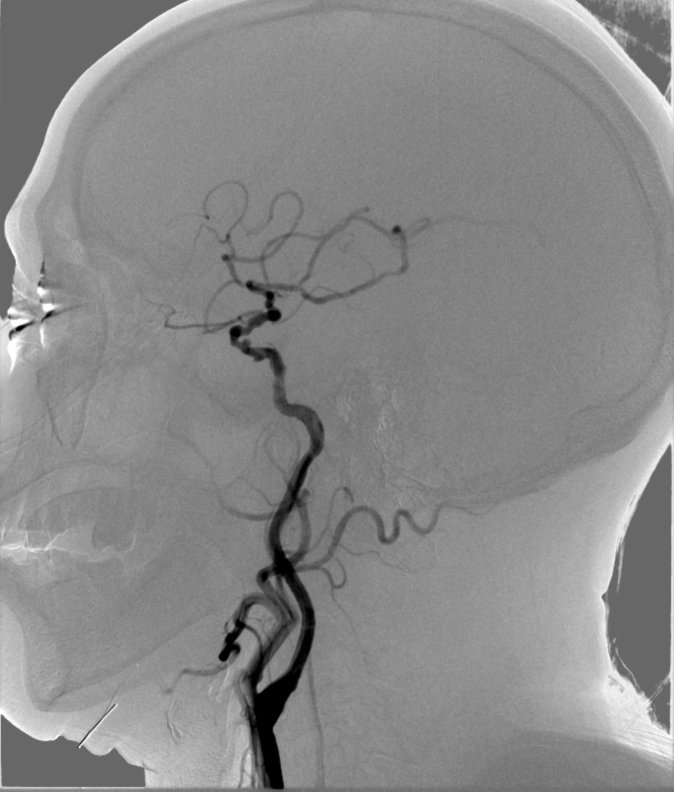

➤ 左侧锁骨下动脉造影:左侧椎动脉优势,V1段迂曲,V4段多发斑块形成,左侧大脑后下动脉开口狭窄约50%;左侧大脑后动脉P1段狭窄约70%;基底动脉近端、中段弥漫性狭窄约70%。

动脉长鞘怎么置入【康德莱医械】经桡介入LA长鞘+Sim II通路组合处理颈内动脉狭窄_https://www.jmylbn.com_新闻资讯_第12张

右侧锁骨下动脉造影:右侧椎动脉V1、V2段斑块形成,V4段远端狭窄约70%。